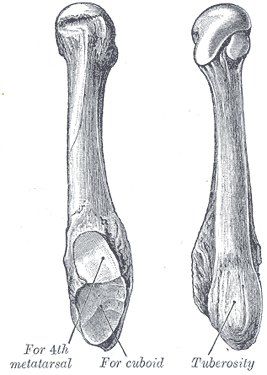

A Jones fracture is a fracture in the meta-diaphyseal junction of the fifth metatarsal of the foot.[1] The proximal end of the metatarsal, where the Jones fracture occurs, is near the midportion of the foot, on the fifth ray (of which the 5th toe belongs). Those who sustain a Jones fracture have pain over this area, swelling, and difficulty walking. The fracture was first described by orthopedic surgeon Sir Robert Jones who sustained this injury himself (while dancing) and reported it in the Annals of Surgery in 1902.[2]

A patient with a Jones fracture may not realize that a fracture has occurred. Diagnosis includes the palpation of an intact peroneus brevis tendon, and demonstration of local tenderness distal to the tuberosity of the fifth metatarsal, and localized over the diaphysis of the proximal metatarsal. Bony crepitus is unusual.

For several reasons, a Jones fracture may not unite. The diaphyseal bone (zone II), where the fracture occurs, is an area of potentially poor blood supply, existing in a watershed area between two blood supplies. This may compromise healing. In addition, there are various tendons, including the peroneus brevis and fibularis tertius, and two small muscles attached to the bone. These may pull the fracture apart and prevent healing.